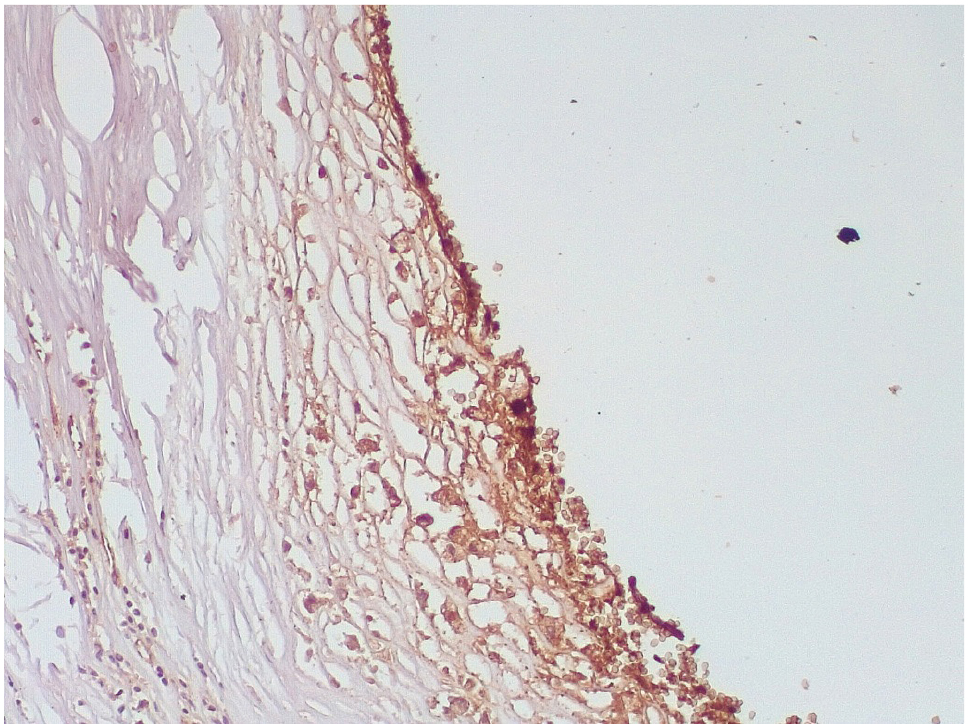

Обращало внимание, что в местах «оголенного» эндотелия КА отмечалась слабая экспрессия белка CD31, что указывало на выраженные дистрофические и некробиотические изменения клеток (рис. 2). При этом экспрессия ФВ была яркой, выраженной на всем протяжении интимы КА (рис. 3).

Рис. 2. Слабая экспрессия белка CD31+ в клетках эндотелия КА в зоне десквамированного эндотелия (1–3-и сутки). Иммуногистохимическая реакция к CD31. Ув. ×200

Рис. 3. Гиперэкспрессия ФВ в клетках эндотелия КА (1–3-и сутки). Иммуногистохимическое исследование с антителами к vWF. Ув. ×200